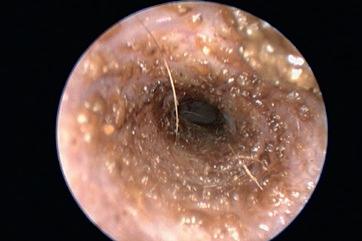

Virbac presenta Cortotic, el nuevo tratamiento de primera línea frente a la otitis externa eritemato-ceruminosa para perros. Su principio activo es la hidrocortisona aceponato, de potente actividad glucocorticoide intrínseca y con una baja disponibilidad plasmática, por lo que los acontecimientos adversos sistémicos son limitados.

Cortotic es un spray delicado con el oído muy fácil de usar, con una cánula atraumática que permite una pulverización fina para una aplicación uniforme en el conducto auditivo. La dosis recomendada es la misma independientemente del peso del perro: dos pulsaciones de la bomba dosificadora en cada oído afectado una vez al día, durante 7 días. El tratamiento puede extenderse hasta 14 días. Cortotic ha demostrado reducir el sobrecrecimiento microbiano secundario al priorizar el tratamiento de la inflamación, factor primario de la otitis externa eritemato-ceruminosa aguda, y consigue aliviar prurito y dolor mientras restaura el microbioma normal del oído sin antimicrobianos.

Se presenta en una caja de cartón que contiene un frasco de 16 ml, cerrado con un tapón de rosca y una bomba de pulverización. Antes de la primera administración hay que enroscar la bomba y cebarla. El volumen del frasco permite el tratamiento de dos oídos durante 14 días.